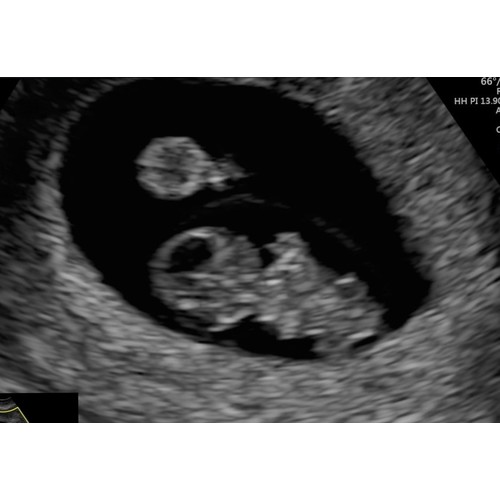

Ligt een beetje aan de verloskundige waar je zit. Bij de verloskundige waar ik bij zit is dit een medische echo. De vitaliteits echo. Waar ze kijken of er een gezonde zwangerschap is en of het een een of een meerling is. Dit doen ze vaak tussen de 7 en 9 weken.